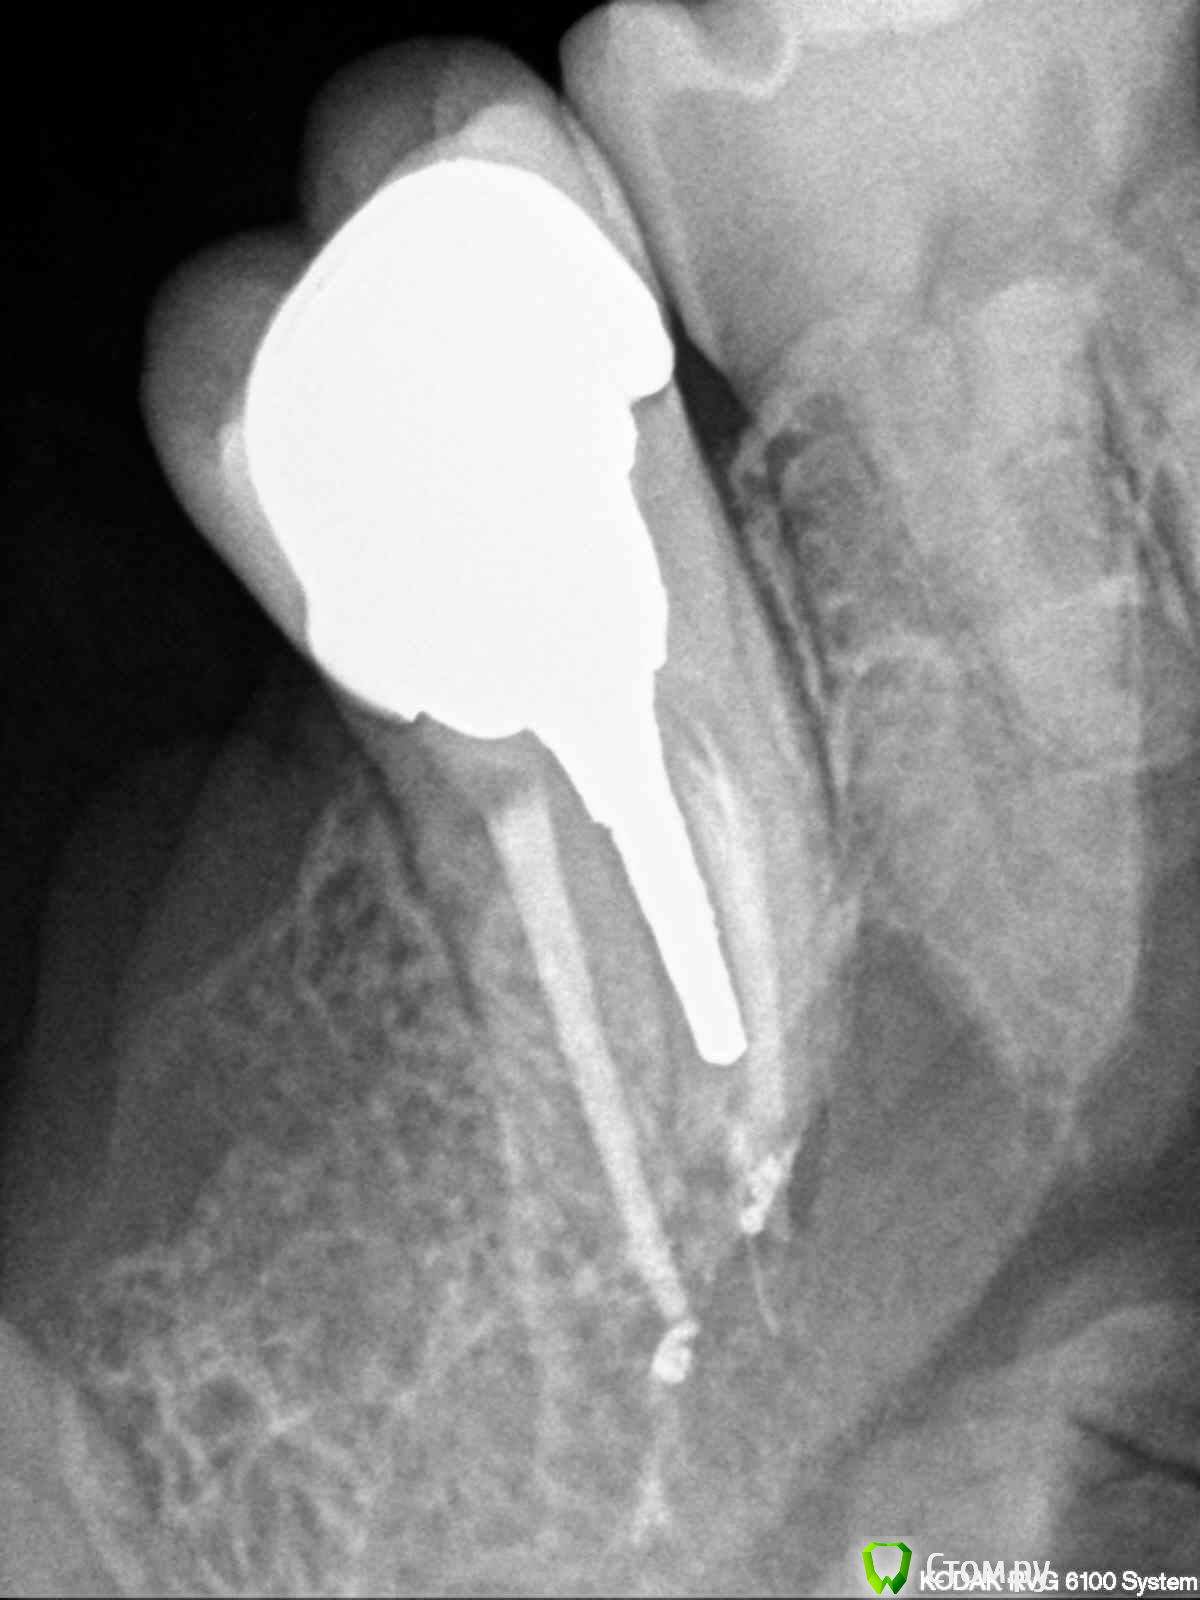

englishlady Опубликовано 3 декабря, 2013 Автор Поделиться Опубликовано 3 декабря, 2013 Спасибо Вам большое за ответы. С фотографиями, навеное, сейчас не получится. Если позволите, задам еще вопрос по 27 зубу. У меня на нем культевая вкладка и коронка. Он у меня стал не сильно ныть. На очном приеме в разных клиниках предположили, что это или из-за недавнего удаления 28 зуба или из-за 38 зуба, который находится в кости. Может быть проблема связана с вкладкой или коронкой, если это можно оценить по прицельному снимку. Снимок прилагаю. заранее спасибо за ответы. Ссылка на комментарий

englishlady Опубликовано 4 декабря, 2013 Автор Поделиться Опубликовано 4 декабря, 2013 Это снимки после пломбировки. Они совсем недавние. Каналы пломбировались прошлой зимой. Коронку одели летом. До октября-ноября зуб не беспокоил. Ссылка на комментарий